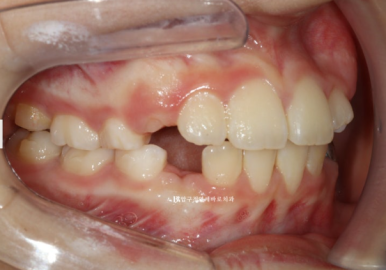

23.1.26

초반에 장치를 끼던 모습입니다.

17번 장치입니다.

아이의 출국스케줄에 맞춰 어태치먼트 없이 초반진료를 진행했습니다.

(그렇지만 출국이 취소되면서 그냥 진료를 계속 진행했습니다.)

아이들은 성인과 달라 초반 움직임에는 어태치먼트가 꼭 필요 없어도 됩니다.